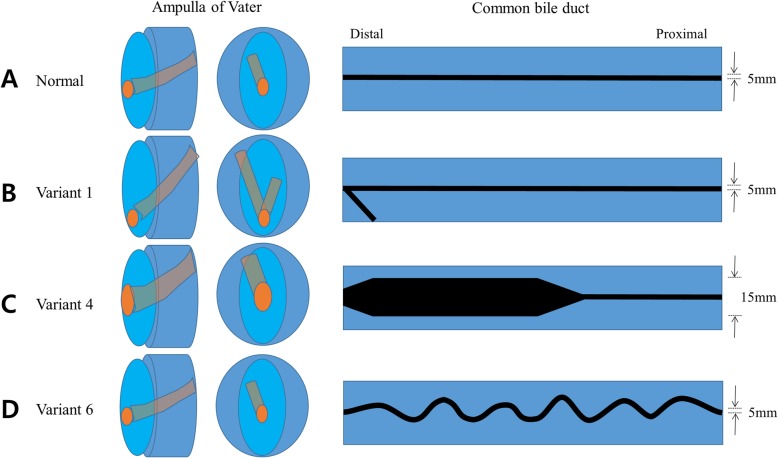

All organ parts of this model were fabricated using silicone molding techniques with 3D printing. Especially, various anatomy of the ampulla of Vater and common bile duct (CBD) were creatively designed for different diagnostic and therapeutic procedures. In order to manufacture each of the designed organ parts with silicone, a negative part had to be newly designed to produce the molder. The negative molders were 3D printed and then injection molding was applied to obtain organ parts in silicone material. The eight different types of ampulla and CBD were repeatedly utilized and replaced to the main system as a module-type.

Digital 3D models of stomach and duodenum were obtained by importing the CT image data to the in-house software by StereoLithography (STL) file format. In addition, a hepatobiliary system, consisting of the ampulla of Vater, pancreatic duct with pancreas, common bile duct (CBD), gallbladder, liver, and intrahepatic bile ducts, was implemented in three dimensions using two open source programs of MeshLab and MeshMixer (Fig. 1a). In this study, endoscopic training in various anatomy of the ampulla of Vater and CBD had to be emphasized. Therefore, removable ampullary and CBD modules were mounted on the base of phantom (Fig. 1b and c). For performing different therapeutic procedures, eight different types of ampullary and CBD modules were separately designed to be utilized and repeatedly replaced on the base of phantom (Figs. 2 and 3).

In order to make the experience of being placed around the duodenal ampulla and the feeling of using various ERCP accessories as realistic as possible, 3D modeling data were obtained from human CT images, as per previous reported studies [ref. 13–ref. 15]. One of important steps in this process was to make the stomach and duodenum. We wanted to make a model where the duodenoscope could be inserted in a sequence that followed from esophagus, stomach, and duodenum, but since silicone material was not elastic and stretchable like the human stomach, we decided to cut the stomach for easy insertion of duodenoscope around the duodenal ampulla and omitted the shortening step. Therefore, insertion of the duodenoscope was not difficult, but the direction of the fluoroscopic image had to be inevitably adjusted because of the difference in direction as compared to an actual human (Fig. 5). Another important step in the designing process was to make the ampulla and CBD in various shapes. If this part could be made into various shapes, it could be implemented for various training models and disease models. In order to resolve this issue, we implemented a new 3D printing method to make these parts in various forms, and to connect them to the main body in a module-type assembly format. Another important step was to implement the sphincterotomy model. For the new model to be appealing and used widely in future, it was necessary that it should be more convenient, cost-effective, and reusable than the previous models. As mentioned for other modules, it had to be easily assembled with the main body, electrically operated, easy to store, and relatively inexpensive. Because the present silicone-material phantom utilizes injection molding technique, it can secure many economic benefits in re-production. Since re-production requires only silicone materials and injection molding efforts, we can save the cost of designing for positive phantom model and negative molder model, and the cost of 3D printing of negative molder as well. Therefore, it is possible to reproduce the same phantom at a price of one-third. Because the present phantom has modular configuration, in addition, it can be implemented with minimal efforts of designing and 3D printing for additional variant designs. While looking for suitable material, the curved Vienna sausage met all the conditions for eligibility and could be used in variable sizes and shapes. Also, it is very similar to the practice in the human body, and creating the sphincterotomy model was a very positive and reaffirming experience.